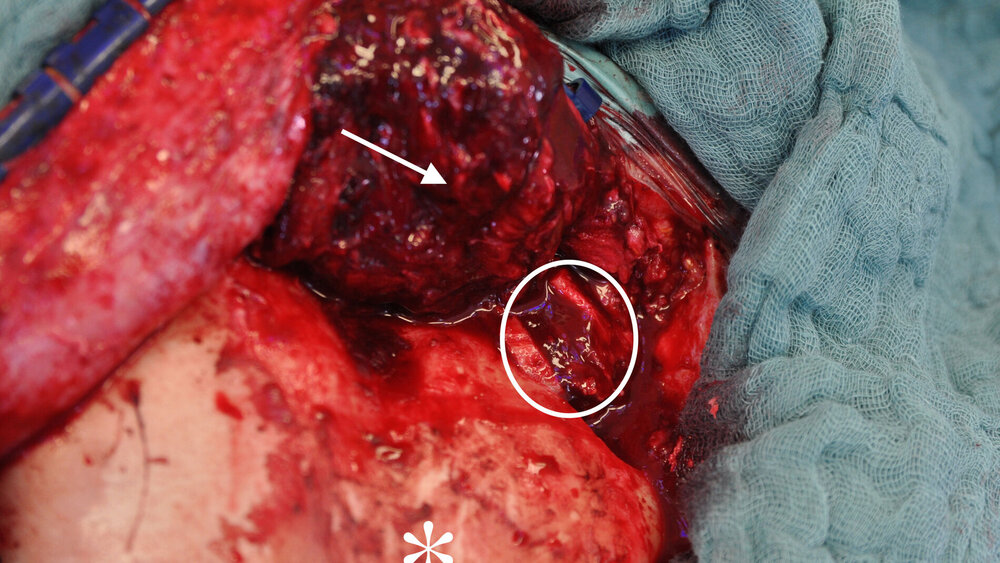

Zufallsbefund eines Riesenzelltumors bei langjähriger Bruxismus-Patientin